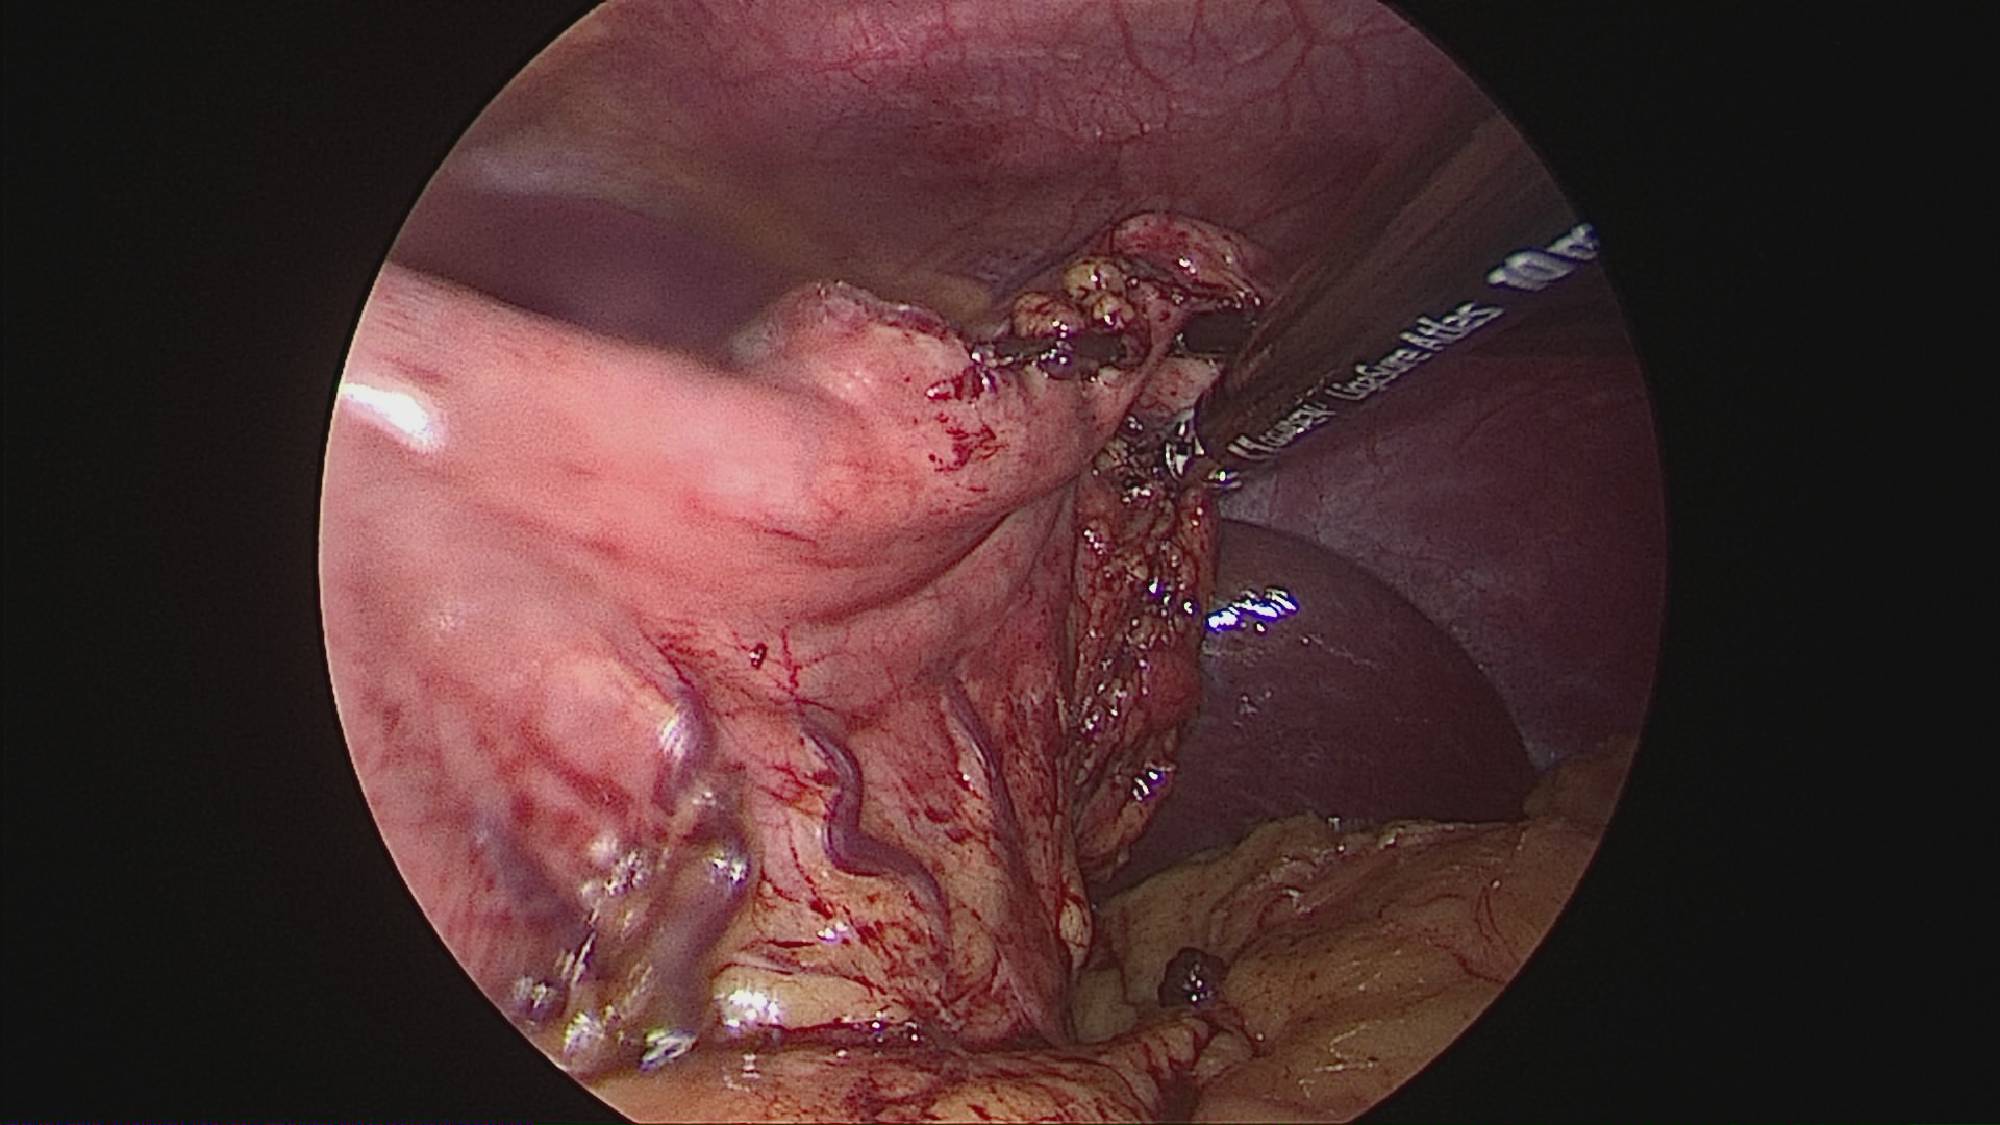

Gastrectomia longitudinală (gastric sleeve) este o intervenție care produce scăderea în greutate prin două mecanisme: restrictiv (îndepărtează o mare parte din stomac lăsând un rezervor de 80-120 ml) și hormonal (prin extirparea fundului gastric se reduce semnificativ secreția hormonului foamei, grelina).

Operația ”de micșorare a stomacului” se realizează miniminvaziv (laparoscopic) și constă în îndepărtarea marii curburi gastrice cu păstrarea antrului gastric și a micii curburi sub forma unui tub calibrat pe o sondă.

Tehnica aduce beneficiile chirurgiei laparoscopice, durere redusă, externare în primele 48 ore de la intervenție. Avantajul său constă în confortul oferit pacientului care prezintă senzația de sațietate rapid prin umplerea unui stomac de doar 100 ml, reducerea senzației de foame prin suprimarea secreției de grelina. De asemenea, nu modifică traseul alimentelor, nu exclude segmente digestive din circuit și pierderea excesului ponderal poate ajunge până la 100%.